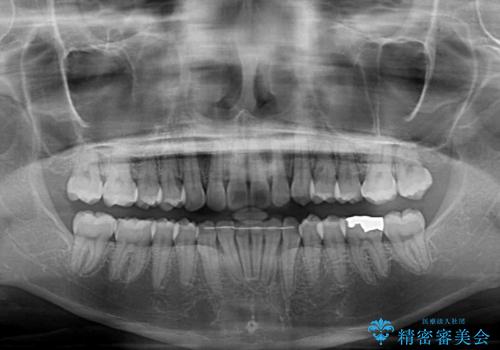

- 上下のクロスバイトと前歯のデコボコを気にして来院された患者様です。

インビザラインを用い、IPR(歯と歯の間を削る)と歯列全体を拡大させることで、歯並びを整えていくこととしました。

下の歯が隠れてしまうほどでしたが、深い咬み合わせも改善され、顎への負担も軽減されました。